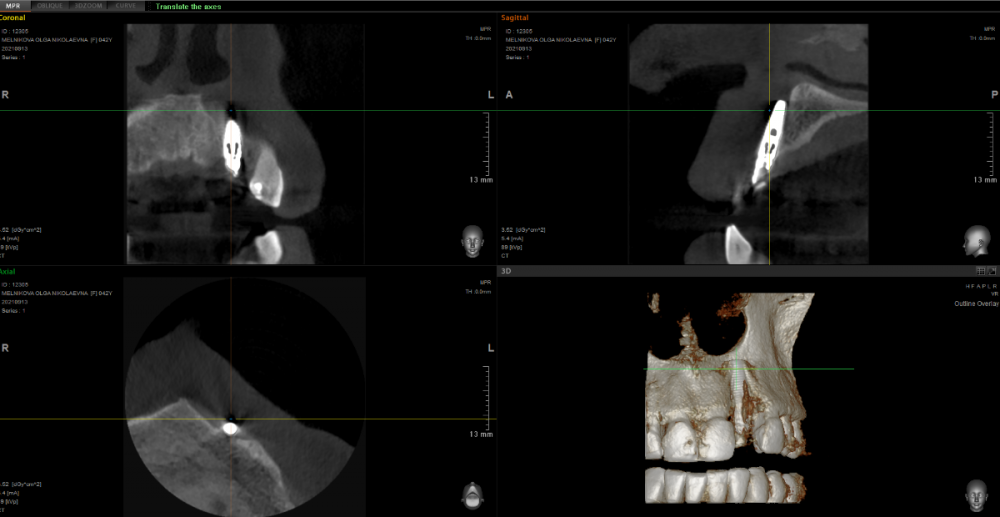

МОН Опубликовано 14 сентября, 2021 Автор Поделиться Опубликовано 14 сентября, 2021 Добрый вечер. Сделала вчера КТ зубов 21, 22, 23. Прилагаю часть срезов. Ссылка на комментарий

red_butler Опубликовано 15 сентября, 2021 Поделиться Опубликовано 15 сентября, 2021 2 минуты назад, МОН сказал: Интересно к чему я должна быть готова? к удалению импланта 1 2 Ссылка на комментарий

It'sGeorgy Опубликовано 15 сентября, 2021 Поделиться Опубликовано 15 сентября, 2021 Тему надо переименовать на «для чего делать КТ после имплантации и почему оптг в хирургии - бесполезная трата времени и денег» и показывать в ВУЗах. 1 Ссылка на комментарий